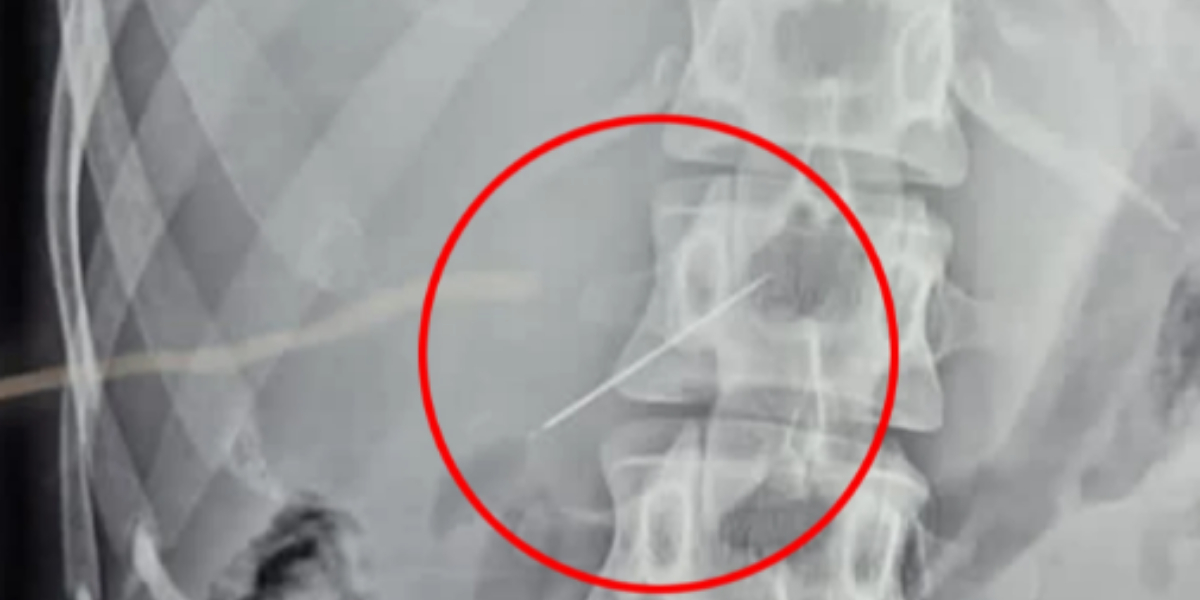

After being returned home after 10 days of several tests, including sonography, endoscopy, X-rays, and CT scans, a final ultrasound discovered the tiny needle embedded in her liver.

She was hurried into surgery once the needle was discovered to remove the object that was causing her anguish.

According to Jam Press, the procedure to remove the needle took two hours and utilised keyhole surgery, which requires only a small opening.

The procedure was videotaped, making it the first time a needle- or pin-removal operation was performed utilising telescopic surgery — an operation performed in the abdomen through small incisions with the use of a camera.